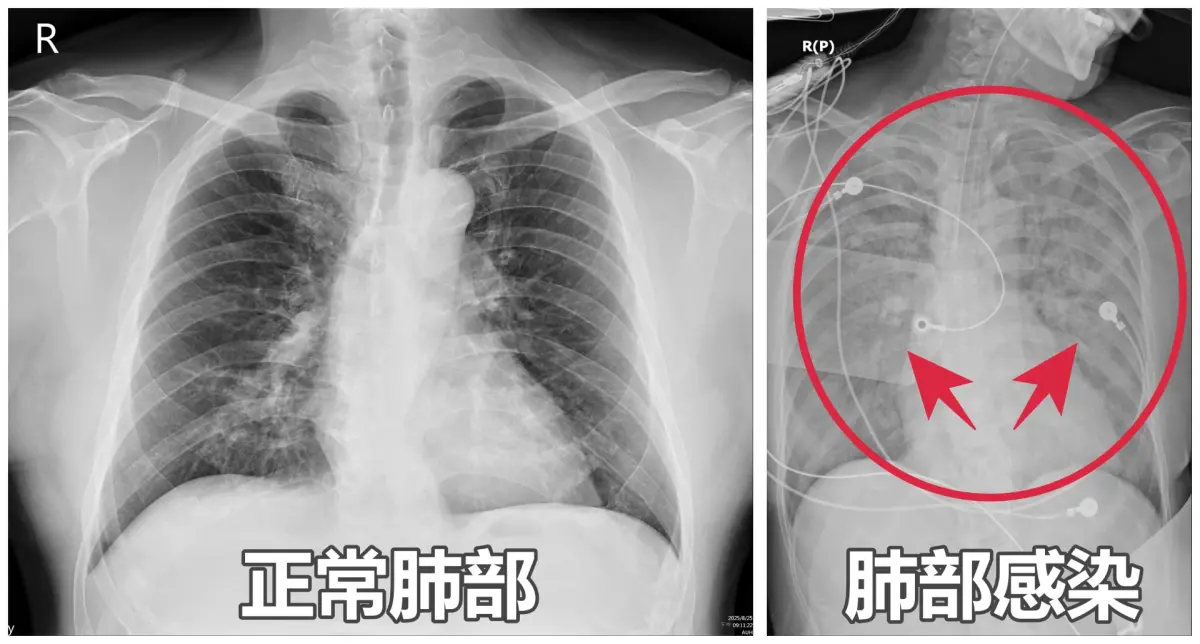

亞洲大學附屬醫院醫師謝逸安表示,65歲李姓闆娘最近嚴重嗜睡、咳嗽、胃口差,被家人形容「像靈魂出竅」,日前因全身無力送急診,檢查發現血氧僅剩90%,且X光竟顯示「雙肺一片白」,確診為肺炎,立即送進加護病房,治療整整1週才出院。

▲謝逸安醫師提醒,接種RSV疫苗、肺炎鏈球菌疫苗及流感疫苗,都是降低重症、死亡風險的有效方法。(圖/亞大醫院提供) 謝逸安指出,肺炎不等於新冠肺炎,流感、呼吸道融合病毒(RSV)、肺炎鏈球菌等,都是常見的社區型肺炎元兇,高風險族群包含60歲以上長者、孕婦、幼童及免疫力較低的慢性病患,一旦感染,常迅速出現「大白肺」,甚至併發敗血症。

此外,肺炎依病因可分為細菌性、病毒性、黴菌性及肺結核,治療方式各異,例如細菌性肺炎可用抗生素,病毒性肺炎則依病毒種類而有不同藥物或支持性治療;根據臨床觀察,若患者有喘、咳血或胸痛等症狀,務必立即就醫,以免病情惡化。

謝逸安也說,肺炎造成的痰液會堵塞支氣管與肺泡,影響呼吸,嚴重者恐危及生命,所幸多數患者若經及早診斷與治療均可康復,但不少人誤以為止咳藥便能控制,反而延誤治療,甚至長期住在加護病房。